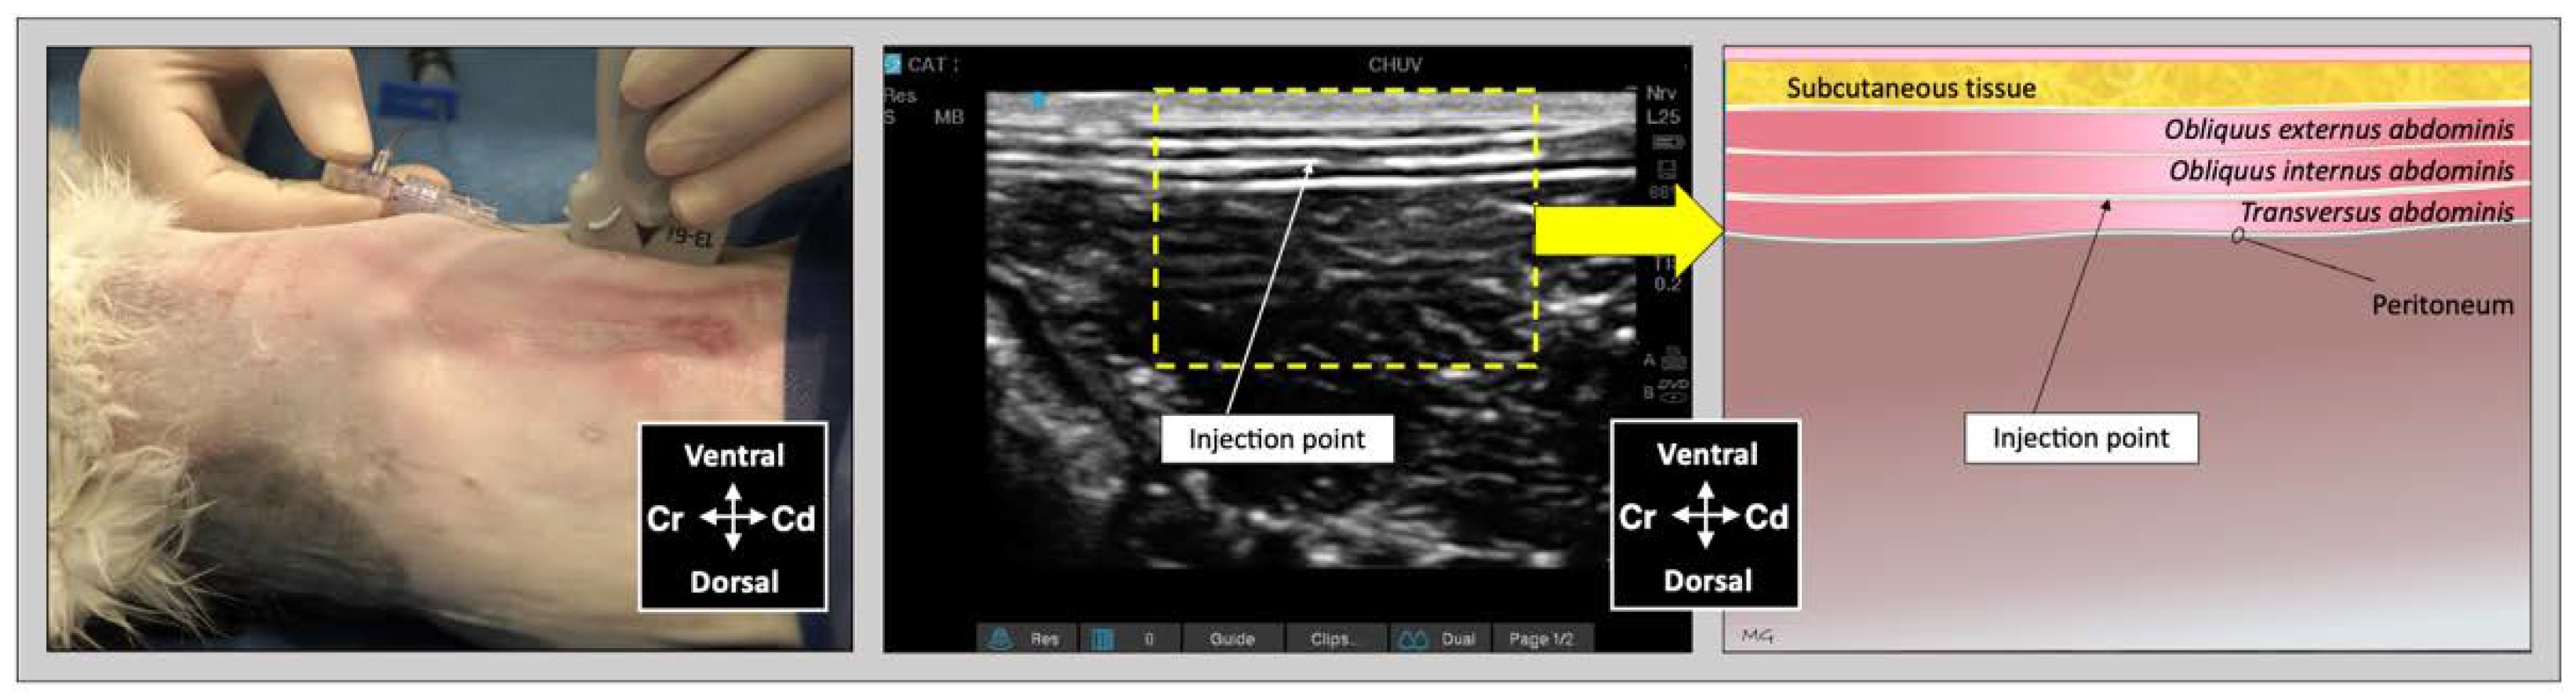

The sonographic appearance of the TAP varied depending on the position of the US transducer and is shown in Figure 6.

Figure 6. Sonographic identification of the TAP in a cat cadaver. At the subcostal region, the m. transversus abdominis (TA) was visualized as the more hypoechoic muscle layer just beneath the m. rectus abdominis (RA), and the TAP was discerned as a hyperechoic line between the two muscles. At the lateral region of the abdomen (at mid-level between axilla and iliac crest, and lateral to the mammary gland line), three hypoechoic layers were observed, corresponding to m. transversus abdominis, m. obliquus internus abdominis (OIA) and obliquus externus abdominis (OEA) from a deep to superficial order. The TAP was identified as a hyperechoic line superficial to the m. transversus abdominis. At the abdominal level, 1–3 cm lateral to the ventral midline (between the lateral margin of the m. rectus abdominis and the medial margin of the m. obliquus internus abdominis) the TAP and the aponeurosis of the m. obliquus internus abdominis appeared as a unique tick hyperechoic line.